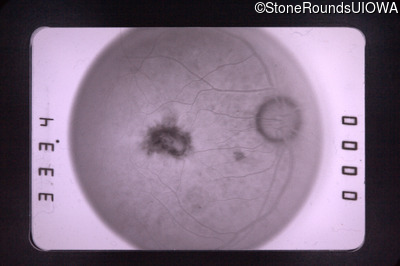

Fluorescein Angiography - Right - 20/30

Exemplar